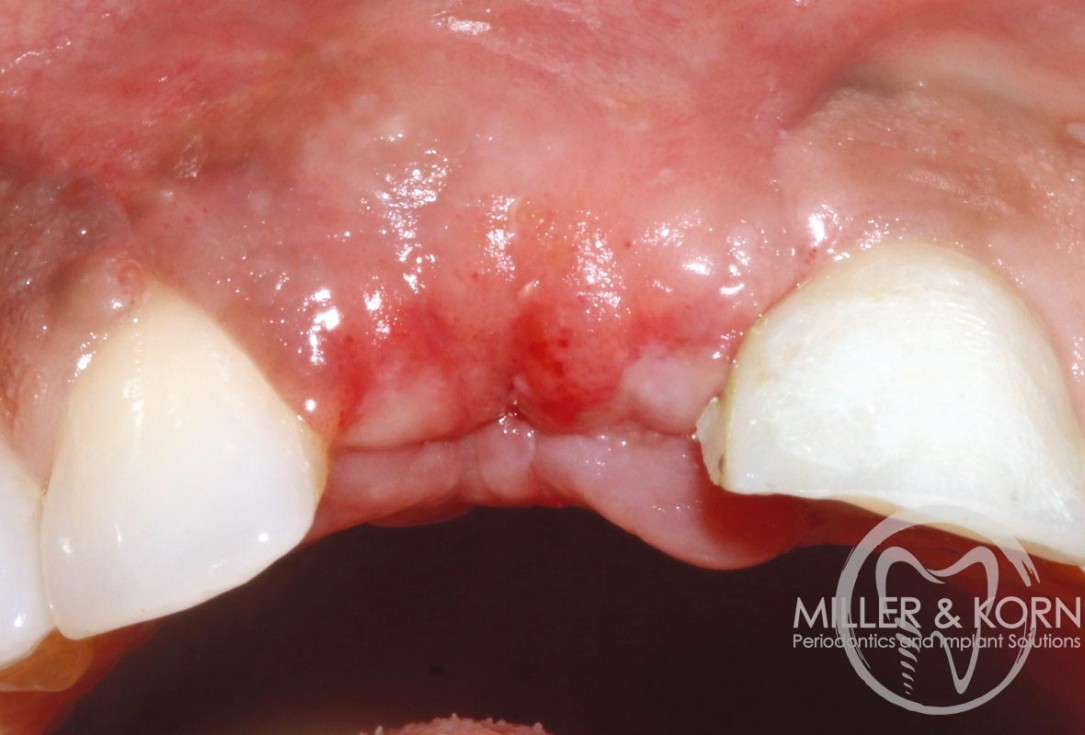

3/22 - Atraumatic extraction of tooth #11Immediate implant placement and regeneration of ridge using an allograft bone ring and Jason® membrane - Drs. Miller and Korn

1/22 - 60-year-old female patient presented with a chronic infection on tooth #11. Since she has a high lip line matching the gingival margins of the adjacent central incisor and creating a root eminence is extremely important. For these reasons, the treatment of choice was an allograft bone ring enabling immediate placement of the dental implant with simultaneous regeneration of her ridge.Immediate implant placement and regeneration of ridge using an allograft bone ring and Jason® membrane - Drs. Miller and Korn